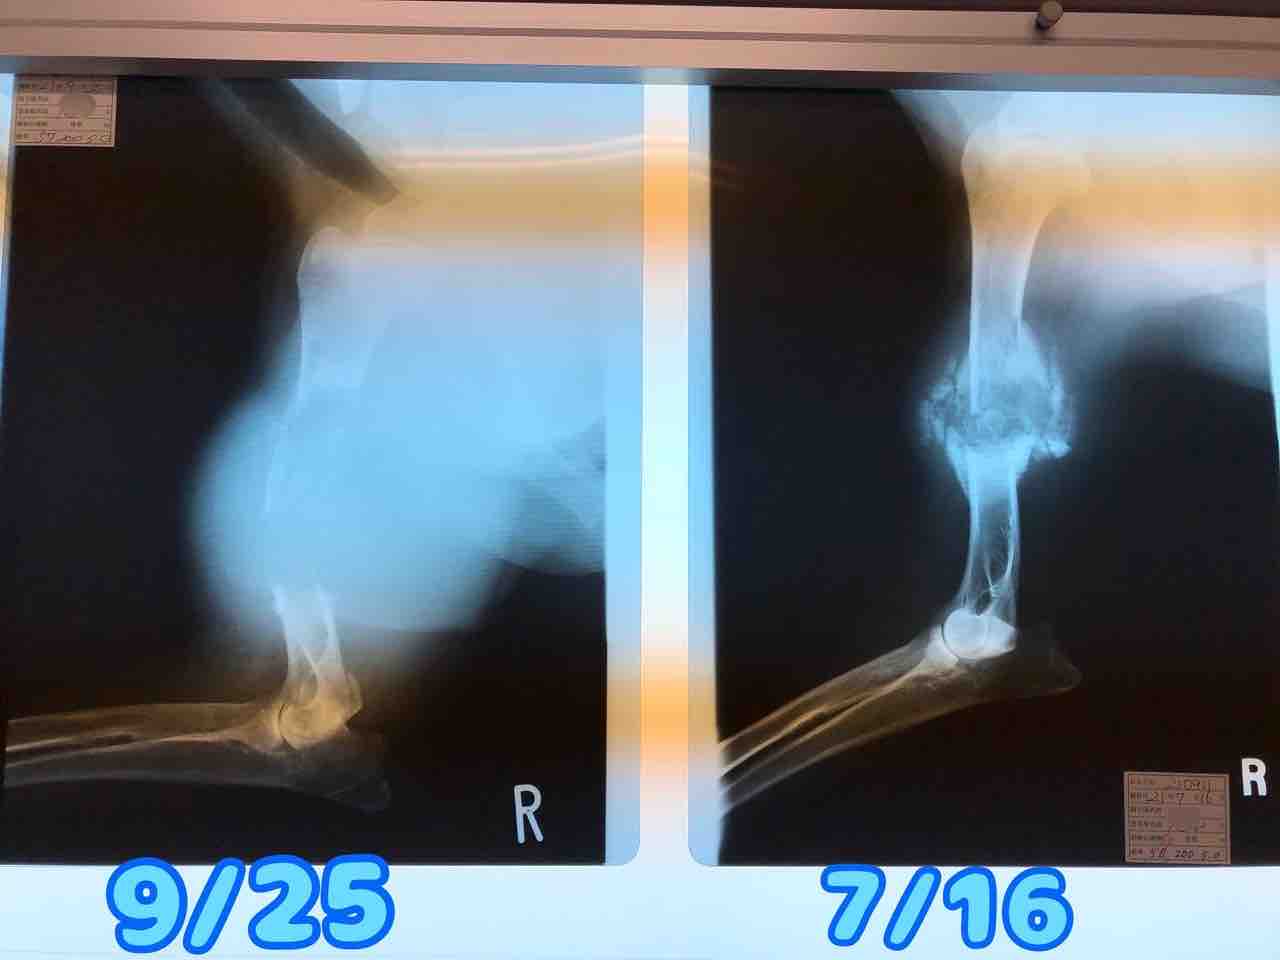

IMG_1073

骨折治療中だった脚が急にボコボコしてきたのが、6月(この写真は6/14)

この脚が…たったの2ヶ月で↓

FullSizeRender

ここまで大きくなり、腫瘍が破裂

IMG_1074

右前脚が骨折したのは6月21日

IMG_1066

たったの3ヶ月でこんなに大きくなってしまいました

骨肉腫が大きくなるスピード、めちゃくちゃ早い